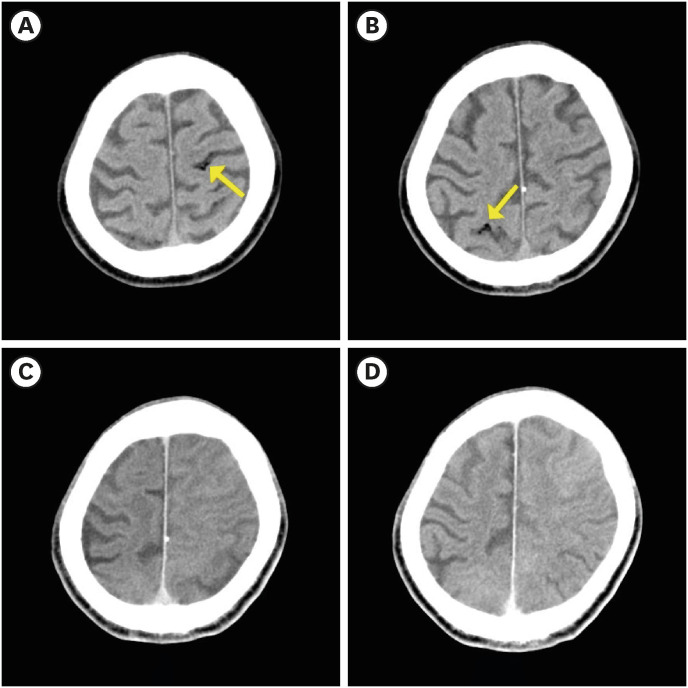

Cerebral air embolism (CAE) occurs in various clinical situations such as surgery, angiography, and hemodialysis; most are iatrogenic. Here we report the case of a 57-year-old man who developed CAE immediately after air-powder abrasive treatment, which is commonly used in dentistry. The patient underwent air-powder abrasive treatment for peri-implantitis, and immediately after the treatment, cardiac arrest occurred and cardio- pulmonary resuscitation was performed. After resuscitation, brain computed tomography performed in the emergency room showed scattered dark density presumed to be air. The day after admission, the patient showed right hemiplegia and a multifocal cerebral infarction was observed on brain magnetic resonance imaging. Therefore, CAE was strongly suspected. After hyperbaric oxygen treatment (HBOT), which started 4 days after the incident, the patient regained consciousness and showed improvement in cognitive impairment, and only grade 4 muscle weakness was observed in the right lower extremity on the manual muscle test. This case highlights the importance of considering CAE as a possible cause of neurological symptoms occurring during clinical procedures involving air, and adds to the accumulation of evidence of therapeutic effects of delayed HBOT.